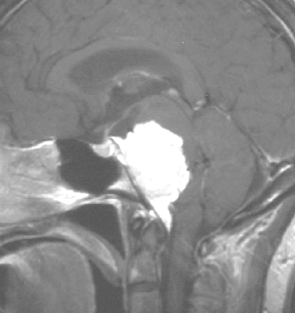

最も見やすいのが,ガドリニウム造影剤を注射して撮影するものです。一般的に髄膜腫は造影剤で白く映し出されます。この腫瘍は左脳側にあります。MRIの軸面という輪切りの写真では左右が逆になりますから注意してください。脳を下から見た図になっています。MRIはいろいろな方向から腫瘍を見ることができますが,右は冠状断という正面から見た図です。よく見ると腫瘍の上と下のはじっこに線状に糸を引いたように造影される部分があります。これをテールサイン(しっぽのサイン)といいます。腫瘍が硬膜に沿って延びている可能性があることを示しています。

手術後のMRIです。腫瘍は全部取れていて後遺症もありません。圧迫されて変形していた脳はきれいに元に戻っていますし脳浮腫も消えました。一般的に若い人の脳ほどきれいに元に戻ります。注意しなければならないのは,少しでも取り残した場合には,何年か後に10%-20%くらいで再発があることです。もちろん完全に取れた時の再発はほとんどありません。